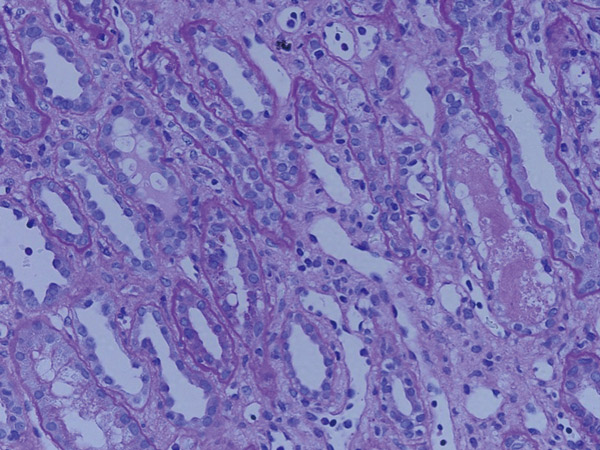

28歳男性。X-6年に健診で尿蛋白を指摘された。X-4年に前医で腎機能の低下を指摘され、腎生検で尿細管間質性腎炎の診断であった。薬剤性、自己免疫性疾患は否定的であり、特発性尿細管間質性腎炎としてステロイド治療を施行し、腎機能の改善を認めた。X-1年当院移植外来を受診。その後腎機能の悪化を認め、Cre 8mg/dL台で、59歳母親をドナーとするABO不一致(O+→A+)の先行的腎移植を施行した。移植後1時間生検は異常を認めず、術後2日目にCre1.27mg/dlまで改善したが、術後5日目でCre3.04mg/dlと急性腎不全を来した。腹部CTで移植腎周囲に液体貯留を認め、尿管膀胱吻合部からの尿漏と考え、再吻合術を行い、術中に腎生検を試行した。超音波で腎腫大およびRIの上昇を認めたため、急性拒絶を考え、先行的にステロイドパルス療法、DSGを投与し、Cre1.4-1.6mg/dLまで改善した。光顕は、糸球体内皮細胞の腫大と増加、また間質に単核球主体の炎症細胞浸潤、傍尿細管毛細血管に炎症細胞を認めた。IFは尿細管基底膜にC3の強陽性を認めた。移植後32日目腎生検は、間質の炎症細胞は著明な改善を認めた。しかし、約半数の糸球体で毛細血管内の炎症細胞停滞や内皮細胞の腫大増加による内腔の狭窄を認めた。その後、腎機能が再び悪化したことから、第76日目に腎生検を施行したところ、尿細管の壊死に加え、広範囲の皮質壊死を認めた。また、軽度の傍尿細管毛細血管炎を認めた。弓状ないし小葉間動脈に著明な線維性内膜肥厚を認めた。Cre 2.79mg/dLと悪化を認め、急性抗体関連拒絶の関与を考え、血漿交換およびステロイドパルス療法、リツキシマブ投与を行った。近年腎移植後の皮質壊死は珍しく、報告する。 |